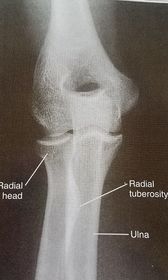

| AP Elbow | ANATOMY: distal humerus - proximal forearm CRITERIA: slight superimposition of proximal radius/ulna humeral epicondyles in profile open joint space POSITIONING: CR perpendicular @ midelbow |

| Medial Oblique Elbow | ANATOMY: proximal radius/ulna, distal humerus, medial epicondyle and trochlea CRITERIA: coronoid process in profile radial head and neck should superimpose the ulna olecranon process seen within olecranon fossa POSITIONING: CR perpendicular @ midelbow |

| Lateral Oblique Elbow | ANATOMY: open joint space, radial head, neck, tuberosity, and capitulum CRITERIA: radial head, neck, and tuberosity are free of superimposition humeral epicondyles and capitulum in profile POSITIONING: CR perpendicular @ midelbow |